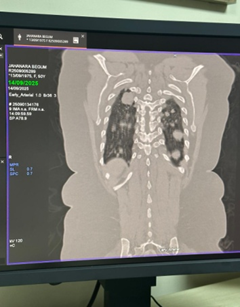

Case Presentation: A 50-year-old female presented with anorexia and cervical lymphadenopathy came for evaluation and management. Chest radiograph and CT scan demonstrated multiple bilateral pulmonary nodules without abdominal organ involvement. Core biopsy of a pulmonary lesion confirmed the diagnosis of NHL, B-cell type.

• Chest radiograph revealed multiple nodular opacities in both lung fields.

• CT chest demonstrated numerous, variable-sized nodules scattered throughout both lungs, with no mediastinal mass, pleural effusion, or consolidation.

• CT abdomen showed normal hepatosplenic and abdominal organ morphology.